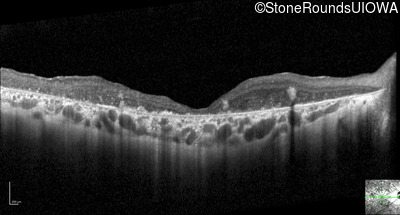

Optical Coherence Tomography - Left - 20/400 sc

Exemplar / OCT Stack